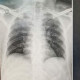

Dari gambaran rontgen pasien tsb apakah ditemukan gambaran yg mengarah ke Pneumonia?

Dari gambaran foto ronsennya tampak suatu infiltrat  suprahiller kanan. Dapat merupakan proses konsolidasi pneumonia non viral. Pada kondisi demikian pemeriksaan fisis paru akan lebih mengarahkan kemungkinan dx.